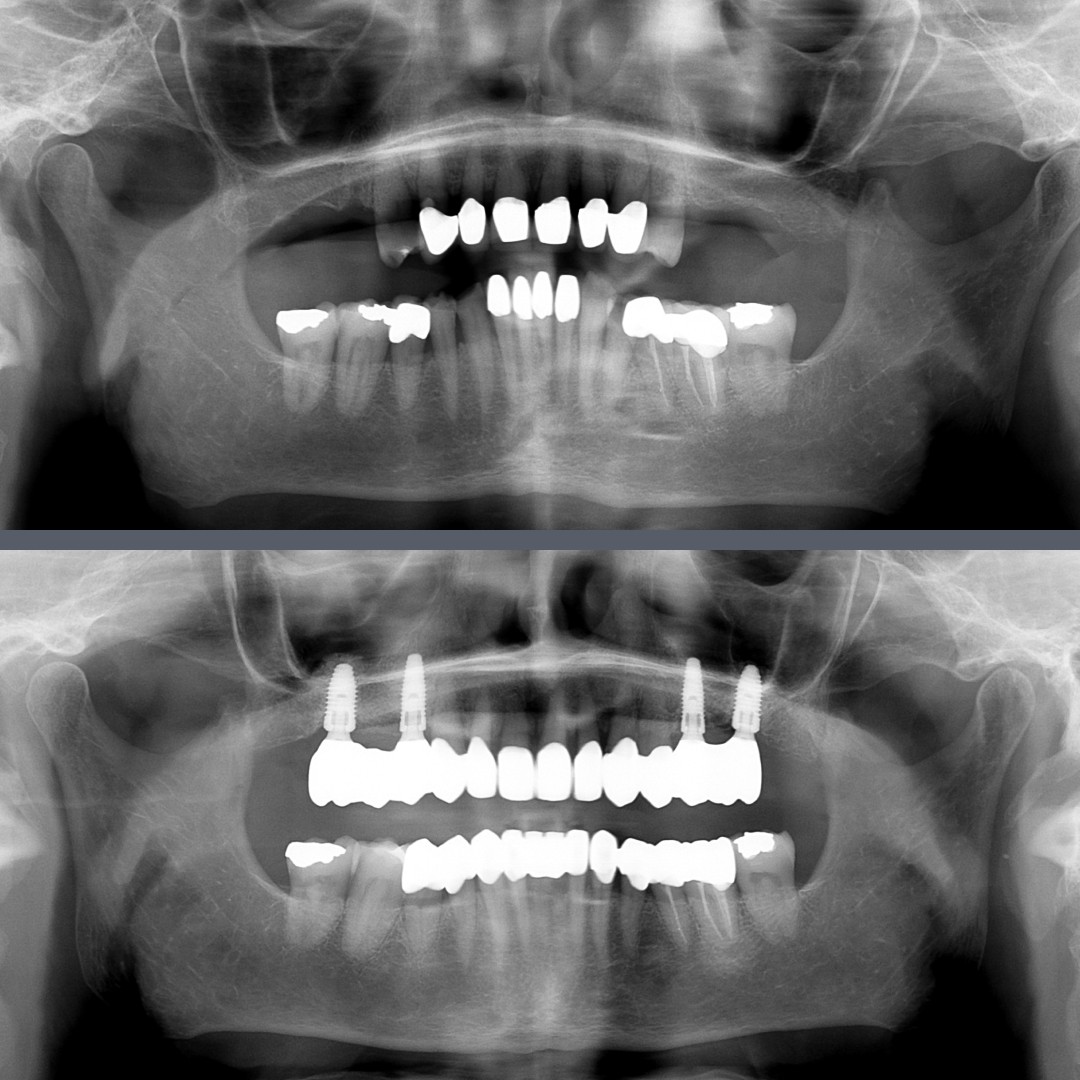

Nearly 70 and ready for a change, our patient came to us with multiple missing teeth and others that were aesthetically compromised. She was seeking a stable, long-lasting solution that would also look and feel natural. A complex, full-mouth rehabilitation involving both upper and lower jaws was necessary.

During the initial stage, we extracted the non-restorable teeth and placed four dental implants in the upper jaw with simultaneous bone grafting.  We also treated several decayed teeth with fillings.

In the second stage, temporary crowns were fitted to ensure a natural appearance and to protect the implants during the healing process.

In the final restorative phase, we created a full set of permanent restorations for both arches. The missing teeth were replaced with zirconia crowns attached to the implants, while the patient’s remaining teeth were also restored with zirconia crowns. Zirconia is a metal-free material that combines exceptional durability with lifelike aesthetics – making it ideal for restoring both front and back teeth.